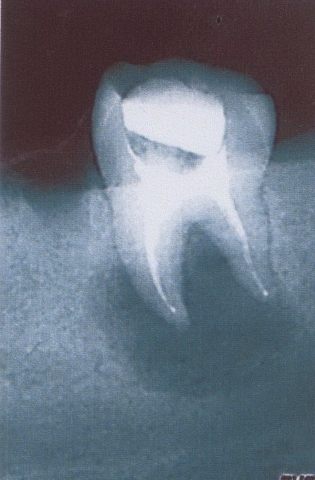

Примеры лечения радикулярных кист челюстей без скальпеля:

Фото: до лечения депофорезом

Фото: после лечения депофорезом